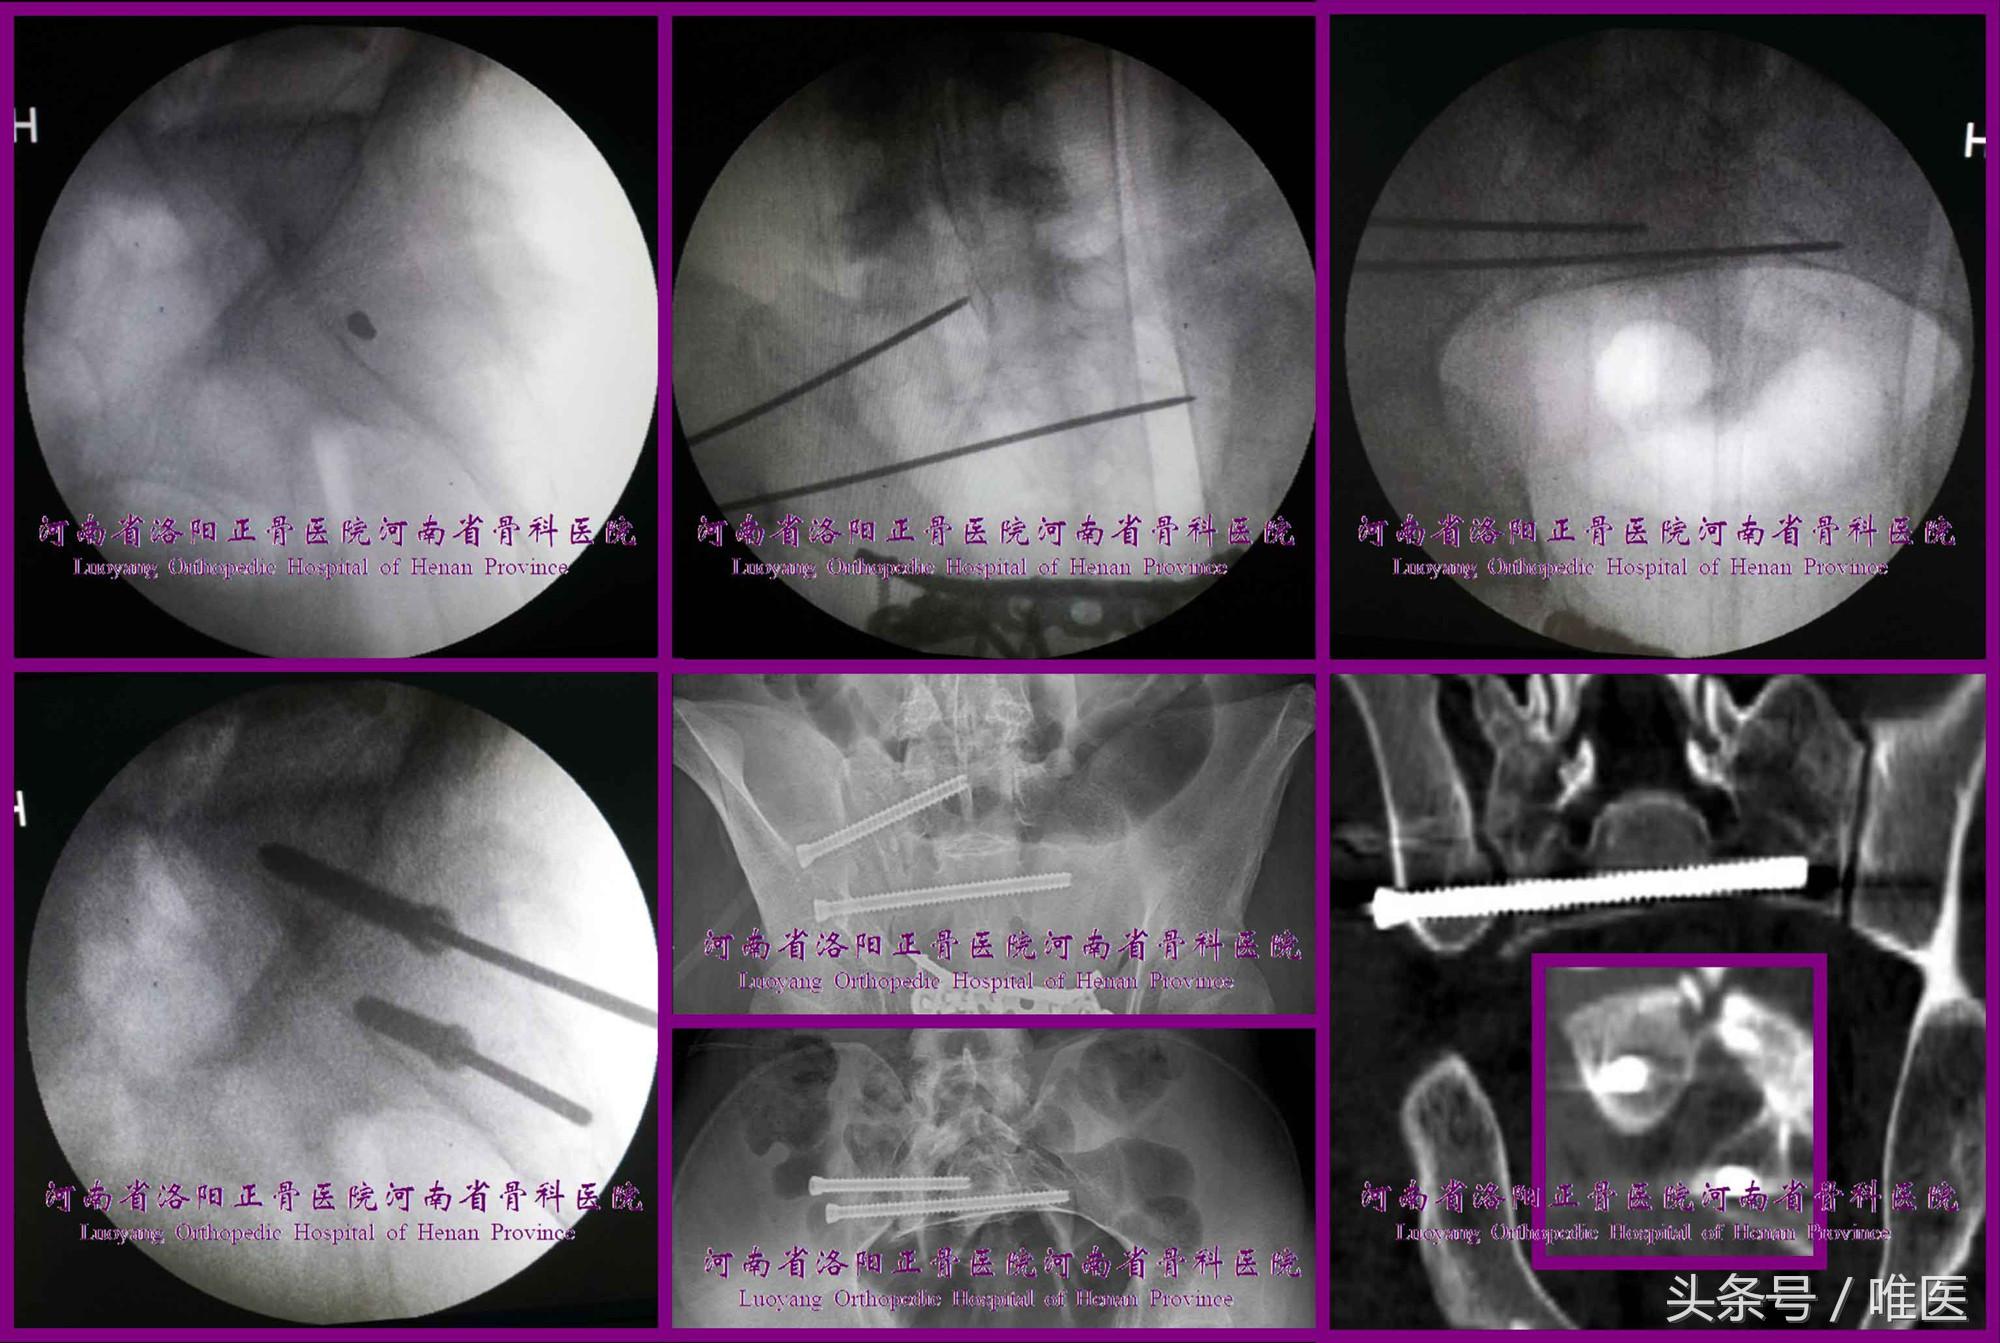

图12. 变异型上骶段骶1骶髂螺钉置入示例(末列第一张图片引自参考文献21)。

2. 骶2骶髂螺钉的置入技术

术前测量确定骶2节段是否存在安全置钉空间。如有安全空间,则按蔡鸿敏等所描述的置钉技术[22]进行置钉操作。(图13)

图13. 变异型上骶段骶2骶髂螺钉置入示例。